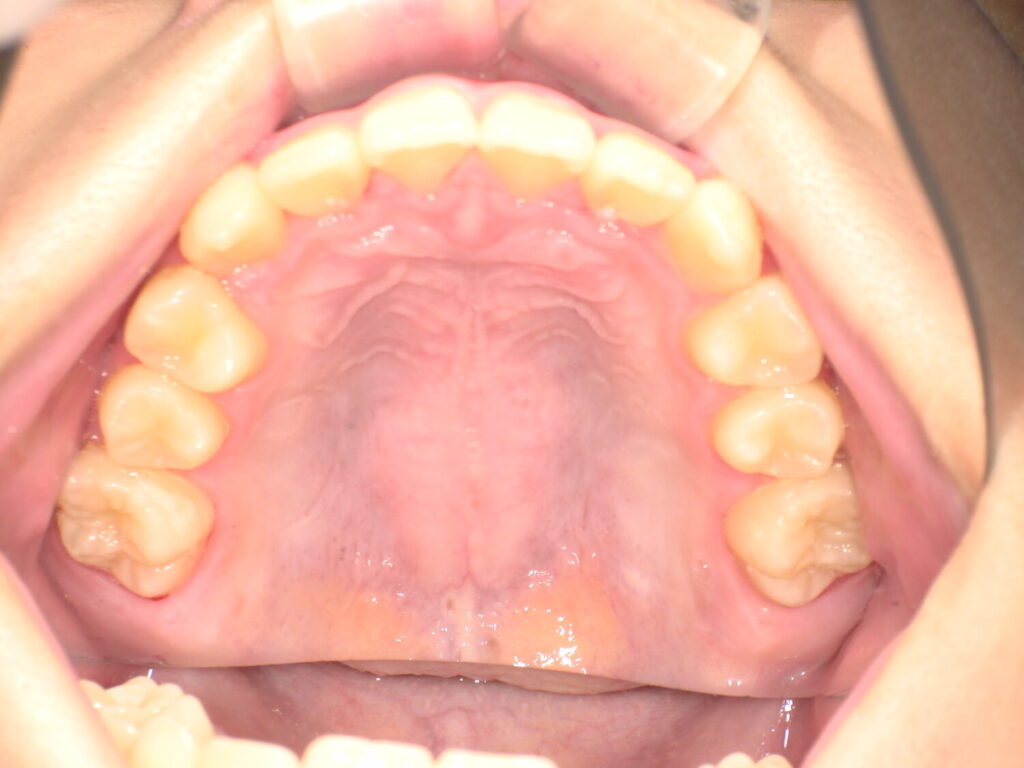

上の歯並びの変化

こちらも3ヶ月の経過です。

がたつきがかなり改善しています。

この頃はまだアクティビティーとマウスピースの装着のみです。